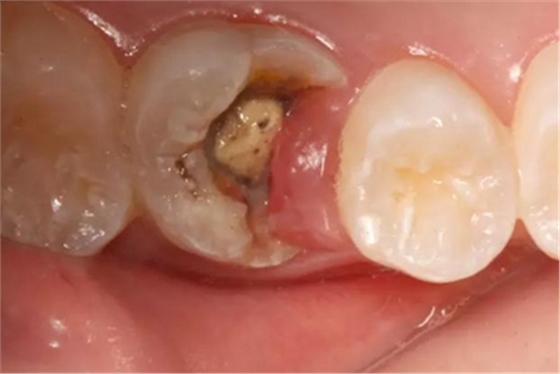

病例一 女性,20歲,大學(xué)生,要求補(bǔ)牙,檢查口內(nèi)可見A6大面積缺損,近中牙齦息肉,拍X片,根管充填物略差,但根周未見明顯陰影,口內(nèi)檢查無叩痛。建議患者冠延長手術(shù)+高嵌體修復(fù)。

患牙遠(yuǎn)中邊緣嵴完整,強(qiáng)度沒有降低,故擬保留遠(yuǎn)中邊緣嵴,高嵌體修復(fù)。首先去除腐質(zhì)及原墊底材料,流體樹脂+3M Z350XT樹脂墊底。局麻下行冠延長手術(shù)。在此需要提及個人的一個觀點(diǎn)。冠延長手術(shù)原則上要求3-6個月以上才能永久修復(fù)。但是個人喜歡后牙肩臺建立在齦上,所以修復(fù)后的修復(fù)體邊緣位于牙齦上方1mm,對牙周的愈合影響較小(如果為齦下邊緣則要慎重),故該患者術(shù)中按照齦上邊緣的設(shè)計(jì)進(jìn)行冠延長手術(shù)。以下為術(shù)中: